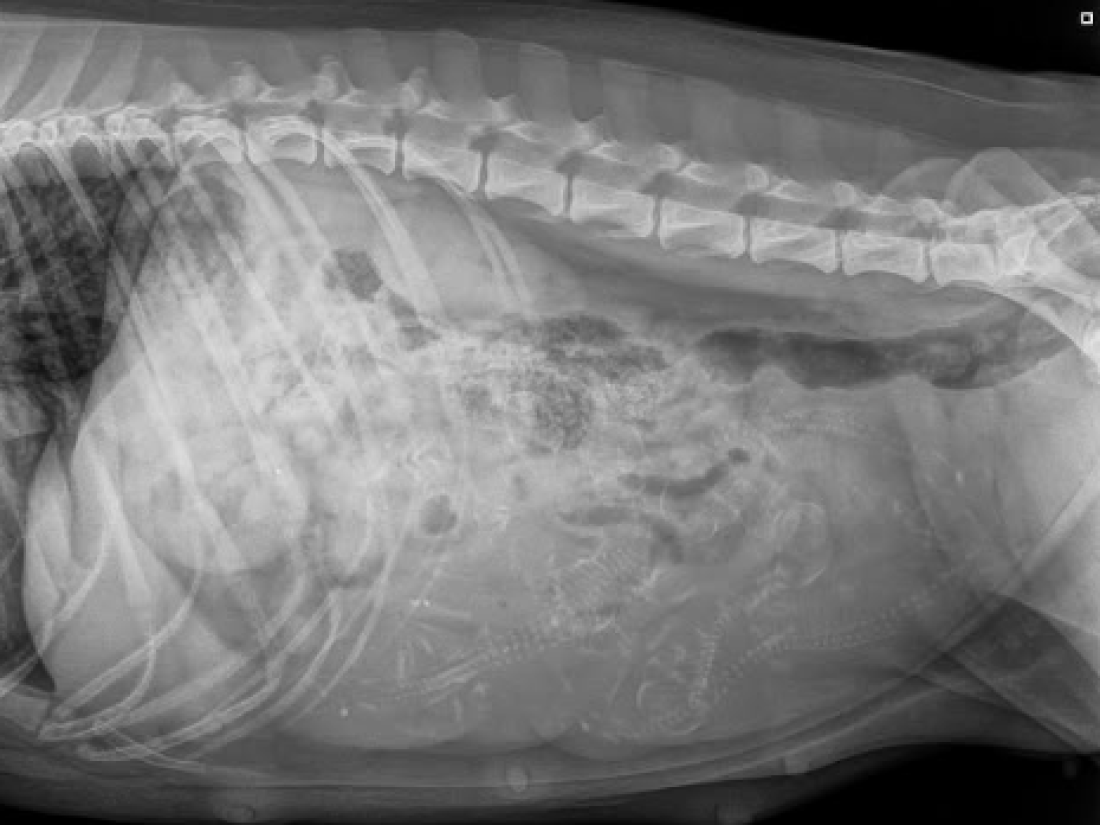

Under gårdagen när vi verkligen konstaterat att varken Doris eller Alfons var intresserade av någon dejt, helt enkelt på grund av att löpet var över - behövde vi tänka om. Vi har ju planerat för detta och har även flera valpköpare som går med längtande hjärtan efter en av våra valpar. ❤️ I samma veva inser vi att Milla också bör vara i höglöp. Vi behövde dividera OM det skulle vara en bra idé. Stämde av med Millas matte såklart. Men efter noggrant övervägande ville vi ge det ett försök. Millas matte hann knappt ut genom dörren innan Milla och Alfons funnit varandra igen 🫣😂 👩‍❤️‍💋‍👨.

Vi fick alltså smida om våra planer i all hast, men nu räknar vi ner efter valpar igen. Inte till vilka valpar som helst - till den helt otroliga kombinationen Milla & Alfons. Ni som följde oss under 2024 vet ju vilken helt fantastisk kombo det blev 😮‍💨. Det finns fortfarande några platser kvar att boka för er som inte vill missa denna chans. Förväntad valpning blir till påsk och leverans runt 11 juni. 🌸